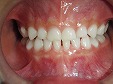

~術前~

床矯正治療(1期治療)

~術中~

~術後~